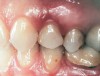

Second-stage surgery was performed after 5 months; healing abutments were placed, and the soft tissue was allowed to heal for an additional 5 weeks. Splinted porcelain-fused-to-metal (PFM) crowns supported by custom gold abutments then were delivered (Figure 5).

Figure 5  Final implant-supported PFM restorations.

Figure 5